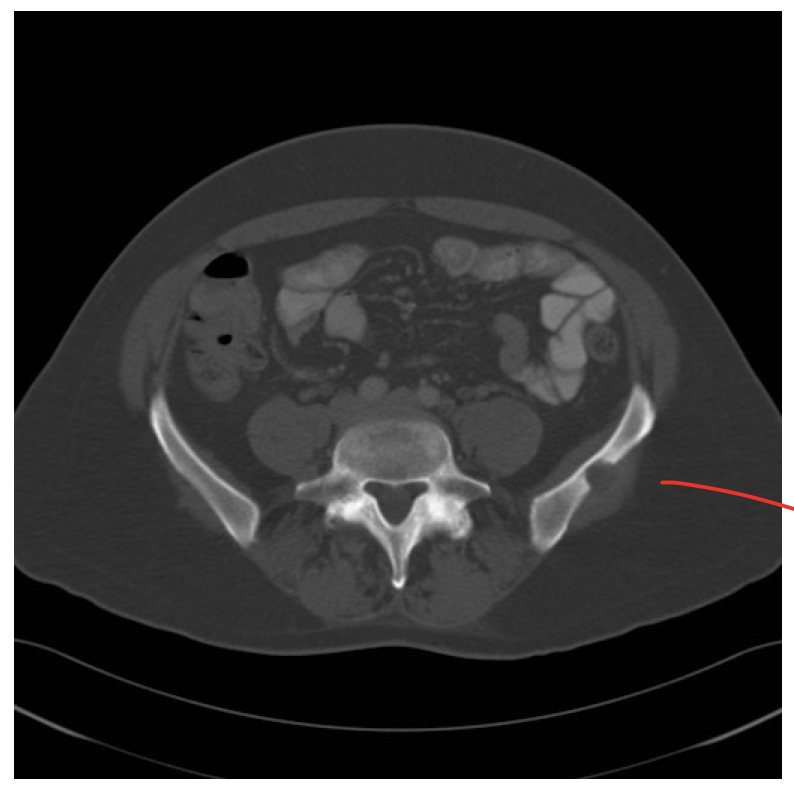

What this be?

Abnormality of iliac spine due to tumor